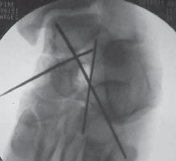

If the closed reduction is unsuccessful, manipulation and reduction under general anesthesia is recommended immediately in the operating room. Percutaneous Reduction

A percutaneous reduction can be an effective and quick next step, particularly if the dislocated talar body is a single fragment.

With the patient in the supine position, a large, firm sterile bump must be positioned under the calf of the patient.

A 4-mm external fixation half-pin is advanced through the posterior tuberosity of the calcaneus, in line with the long axis of the bone, to the subchondral surface of the anterior process of the calcaneus.

Next, a medial-to-lateral 4-mm half-pin is advanced across the dense subchondral distal tibia bicortically.

A final 4-mm half-pin is manually, and carefully, advanced deep into the body of the talus through a 1.5-cm longitudinal incision.

The long calcaneal pin has terrific mechanical advantage with traction to the torn posterior capsule of the ankle.

The surgeon distracts the distal tibial and calcaneal pin while a surgical assistant attempts to reduce the talar body anteriorly using the half-pin as a joystick. Reduction of the Talar Dome Fragment